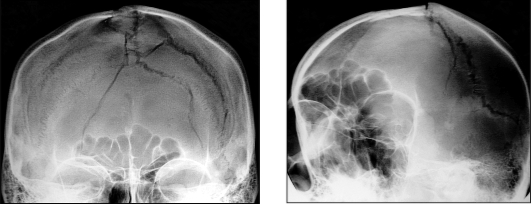

Кроме неврологического обследования, больным с подозрением на перелом черепа проводят обзорную рентгенографию черепа в двух проекциях, КТ и МРТ головы.

·линейные (тонкая линия перелома, без смещений костных фрагментов) - наименее опасные, редко сопровождаются потерей сознания;